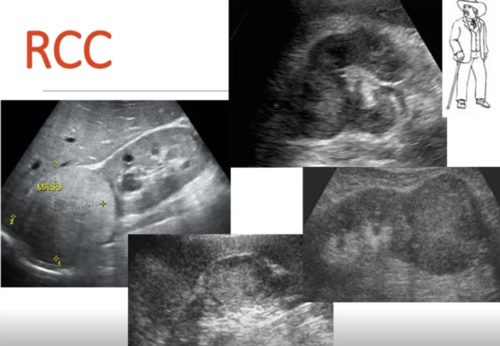

What make up about 90% of all renal cancers?

renal cell carcinoma (parenchyma)- includes adenocarcinomas

Describe the presentation of a patient with renal cell carcinoma.

-*gross or microscopic hematuria*

-flank pain or mass

-fever, weight loss

-solid renal mass on imaging

-night sweats, fever, malaise, weight loss

-*erythrocytosis but anemia is more common*

-*hypercalcemia*

-*stauffer syndrome* - hepatic dysfunction in absence of liver metastasis

What is the best initial test for renal cell carcinoma?

-US because it is inexpensive, without radiation and high sensitivity

-then do CT or MRI

-then *biopsy or nephrectomy*

-bone scan if metastasis is suspected